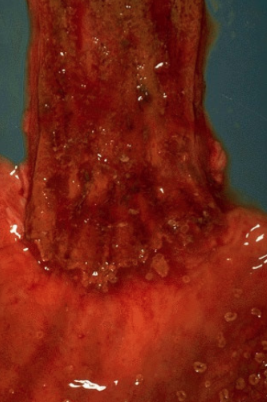

Achalasia